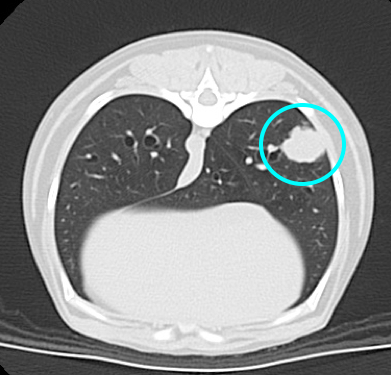

CT撮影検査では右肺後葉に長径1.5~2.0cm程度の腫瘤性病変が確認され、細胞診検査により上皮系悪性腫瘍が疑われました。

画像中央肺野に腫瘤が確認されます。